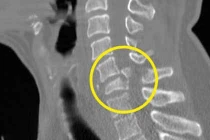

(khoahocdoisong.vn) - Đa phần bệnh nhân bị gãy trật cột sống cổ sẽ bị liệt hoặc tử vong. May mắn một bệnh nhân nữ 70 tuổi đã được phẫu thuật cứu sống không để lại di chứng sau 5 ngày bị gãy trật đốt sống cổ C4-C5 độ III.